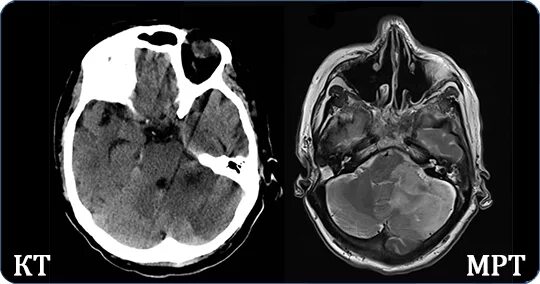

Чем отличается кт от мрт головного